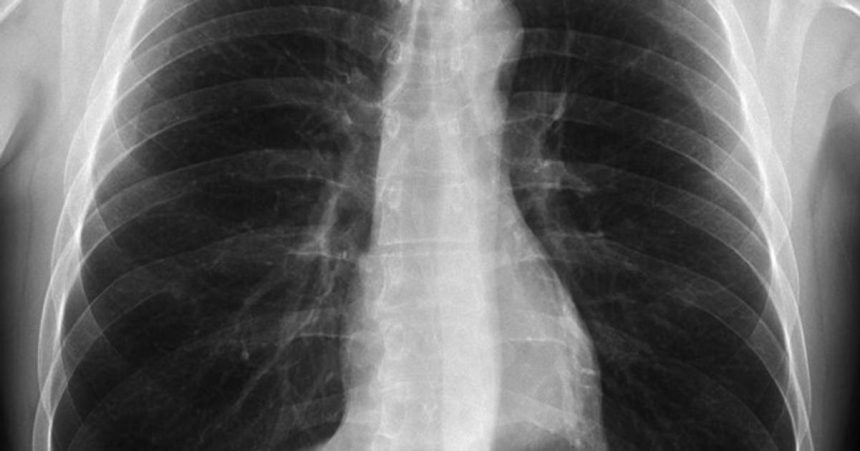

Referencia k umelé inteligencii (AI) ako potenciálnemu faktoru prepúšťania v rôznych profesiách stále rastie. Mnohé predpovede tvrdia, že najohrozenejšie sú profesie s digitálnymi stopami, ktoré môžu byť efektívne analyzované a spracované AI. Príklady popredných kandidátov na nahradenie sú programátori, právnici, účtovníci a rádiológovia. Je však zaujímavé poznamenať, že zatiaľ čo AI dokáže veľmi efektívne spracovávať röntgenové snímky, nepotiahne tým k zániku samotných rádiológov.

Geoffrey Hinton, známy ako „krstný otec” AI a nositeľ Nobelovej ceny za fyziku, varoval, že röntgenológovia sa dostávajú do nebezpečnej situácie, akúsi hranu útesu, nad ktorou sa nachádzajú, no nie sú si toho vedomí. Hinton predpokladal, že by sme mali zastaviť vzdelávanie nových rádiológov, pretože AI by mohla zastúpiť ich professionalitu do piatich rokov. Avšak otázka, prečo sa tak doteraz nestalo, ostáva otvorená.